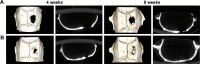

Results: Drug release behavior results of ACS showed that the nanoparticles fabricated in this study could successfully sustain the release of the drug. TEM showed the morphology of the nanoparticles. SEM images indicated that the asymmetric membrane comprised a loose collagen layer and a dense chitosan layer. In vitro studies showed that ACS-CCM could promote the proliferation of BMSCs, and that the degree of differentiated BMSCs seeded on CCMs containing 50 mg of ACS was higher than that of other membranes. Micro-computed tomography showed that 50 mg of ACS-CCM resulted in enhanced bone regeneration compared with the control group.